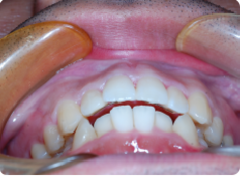

「上の前歯のデコボコを治したい」このような相談は、非常に多いです。

マウスピースで簡単に治せます。他院だと相場で1個につき20,000円前後。

当院は1個につき5,000円です。